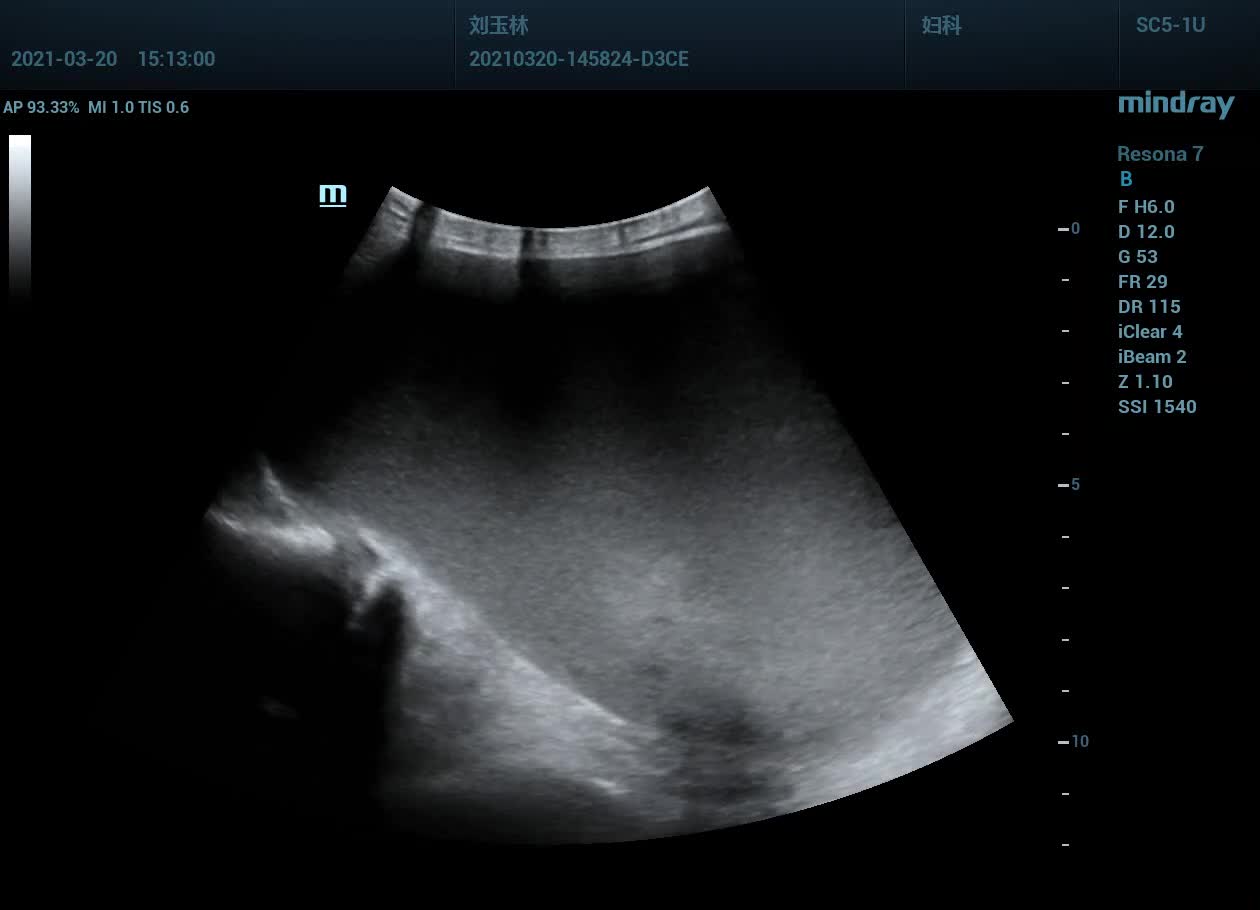

超声所见: